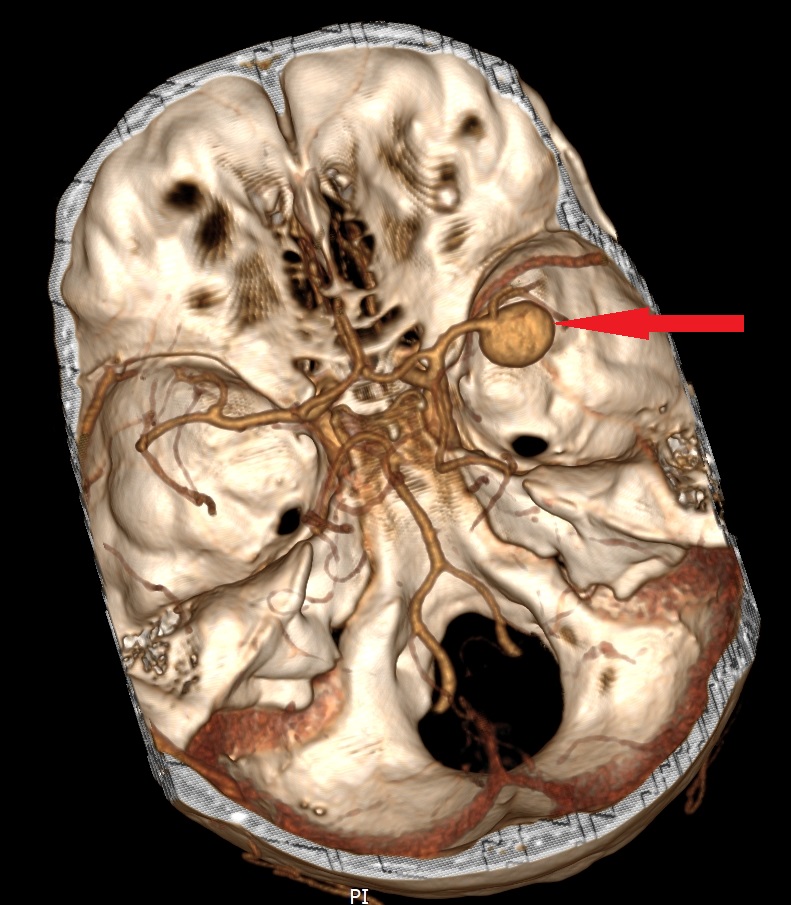

- Zmiany naczyniowe (np. naczyniaki jamiste, tętniaki)